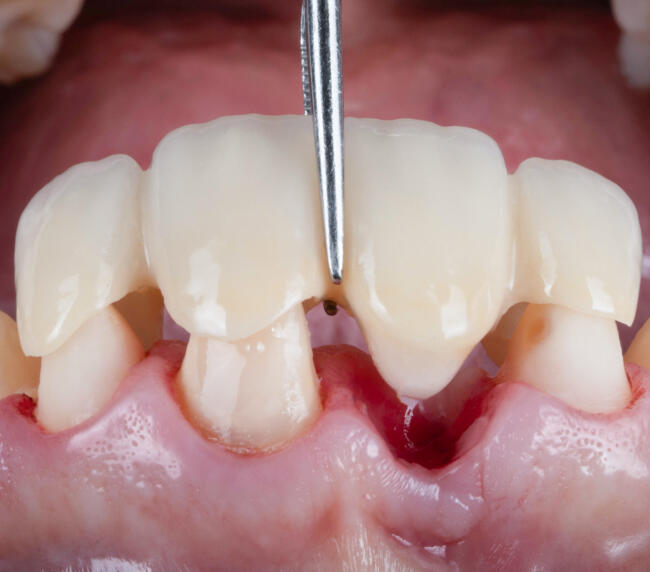

- Șlefuirea dinților de susținere sau inserarea implanturilor

- Amprentă digitală cu scanner intraoral sau clasică

- Proba lucrării și adaptarea funcțională și estetică